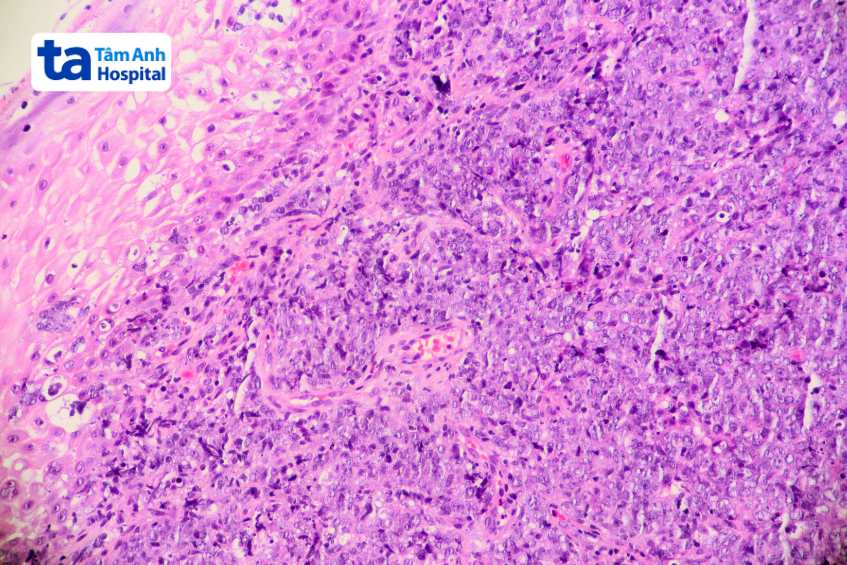

Để xác định số lượng tế bào lympho B trong máu, bác sĩ sẽ chỉ định thực hiện xét nghiệm công thức máu toàn phần. Một số xét nghiệm khác cũng có thể được thực hiện trong trường hợp mắc các bệnh lý liên quan đến tế bào B bất thường, chẳng hạn như dấu ấn miễn dịch tế bào, giải phẫu bệnh và hoá mô miễn dịch mẫu mô hạch hoặc mô tuỷ xương…